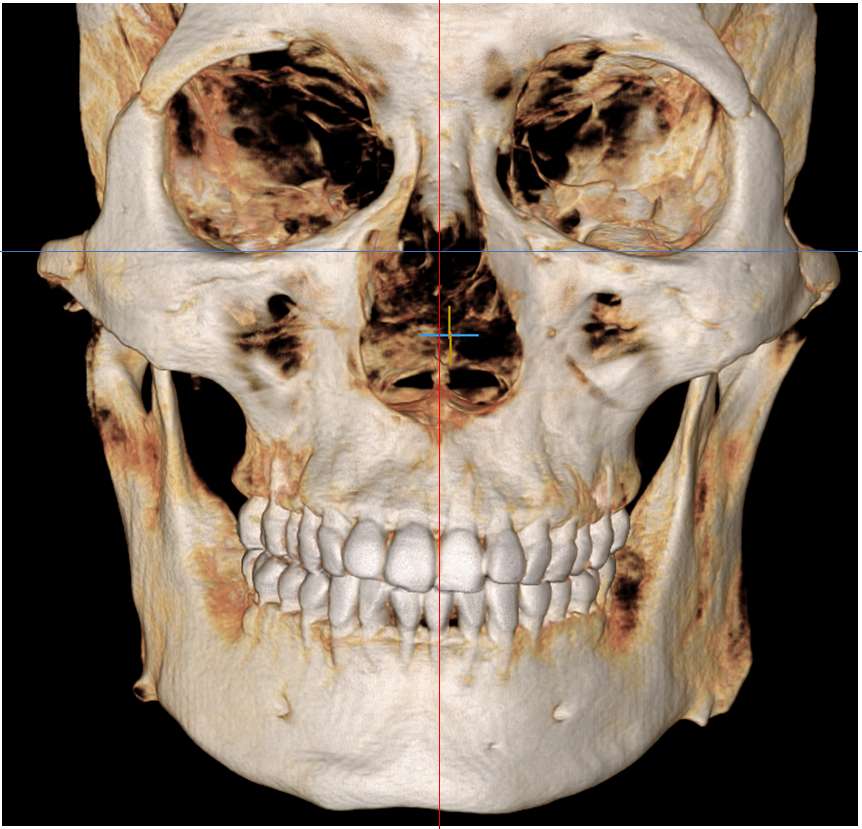

위턱과 얼굴의 정중선을 대비해 보면

위턱이 약간 오른쪽에 위치하며

윗니의 치열 및 입술은

오른쪽이 높게 기울어져 있습니다.

턱 끝이 우측으로 편위 되어 있었습니다.

23.08.17

더불어, 위 어금니 간의 폭경과

아래 어금니 간의 폭경의 비율은 정상으로

확인되었으며,

왼쪽 비강에 상악동염이 관찰되었습니다.